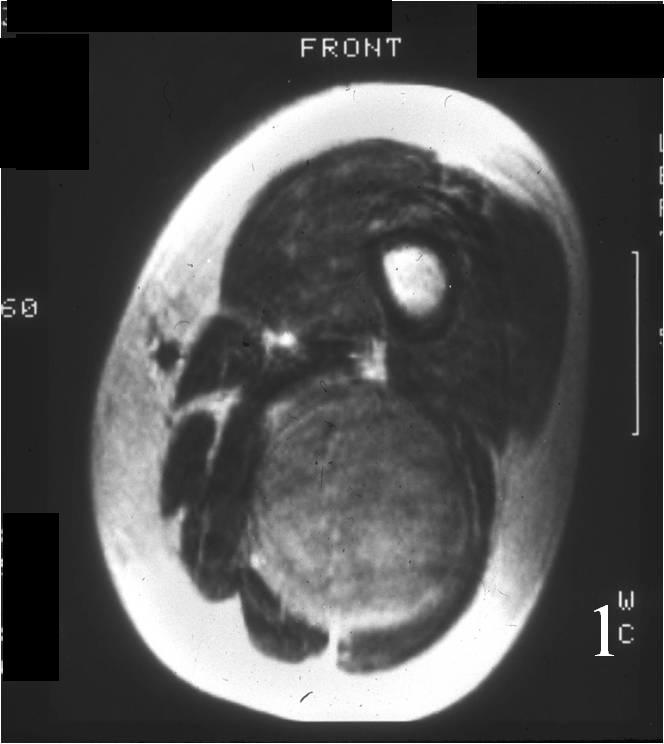

Radiographic imaging is used to help form a diagnosis. These include MRI, CT and Bone Scans.

An example of an MRI is shown.